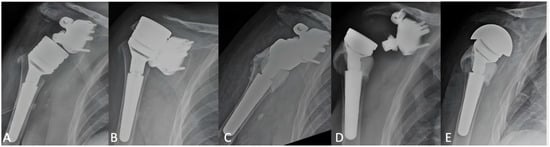

3.2. Radiographic Outcomes